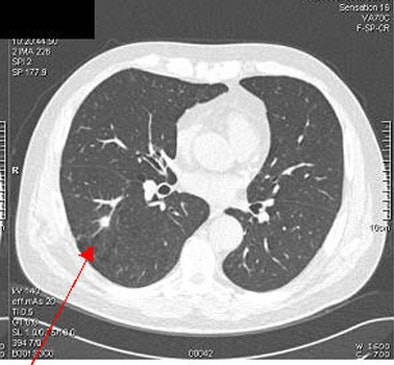

![]() |

The rate of probable lung carcinoma was lower than that seen in the nonrandomized International Early Lung Cancer Action Program (I-ELCAP), or the randomized National Lung Screening Trial, she said. As for other differences, "in the I-ELCAP study, approximately 60% of lung cancers were subsolid lesions, but in our study almost 100% of the lung cancers (were) solid lesions. And this finding is consistent with other literature," Xu said.